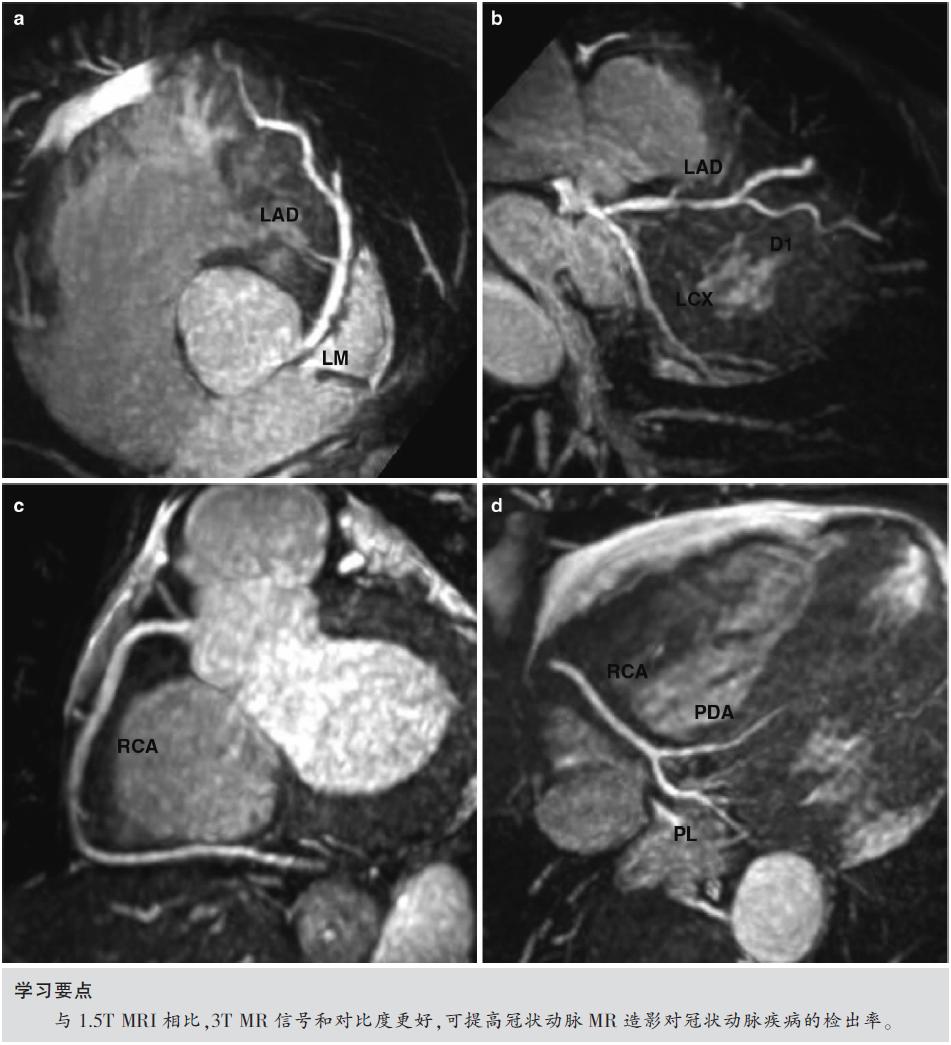

图7.1 1.5T正常冠状动脉受试者,自由呼吸全心CMRA。采用1.5T MR获得非对比增强的三维CMRA图像,采用稳态自由进动(SSFP)序列、导航回波门控、T2预扫描、光谱预饱和反转恢复脂肪饱和(TR/TE,4.6/2.3ms;翻转角度,90°;SENSE因子4;FOV 280mm×280mm×120mm;采集矩阵256×256×80;重建矩阵512×512×160)。

(a)右冠状动脉(RCA)薄层最大强度投影(MIP)图像。(b)左主干和前降支(LAD)薄层MIP图像。(c)RCA的VR图像。(d)LAD和LCX的VR图像。

图7.7 正常志愿者对比增强3.0T全心冠状动脉造影。注射0.15mmol/kg钆喷酸葡胺(Magnevist;Schering,Berlin,Germany)后,通过使用平衡相中的脂肪饱和脉冲获得梯度回波三维CMRA图像(TR/TE,4.2/2.1ms;翻转角度,20°;SENSE因子4;FOV 280mm×280mm×120mm;采集矩阵256×256×80;重建矩阵512×512×160)。

(a)左主干(LM)和LAD的MIP图像。(b)LAD薄层MIP图像,第一对角支(D1)。(c)RCA薄层MIP图像。(d)RCA远端、后降支(PDA)和后外侧支(PL)的MIP图像。